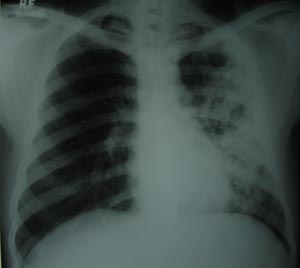

Left mid zone Koch’s infection 4

Right mid zone shows multiple fibronodular opacity, suggestive of unilateral koch’s infiltration. Compared to previous x ray there is a good response in all 3 parameters i.e. clinical, radiological & pathological. Patient is continuing with 3 drug AKT regimen.